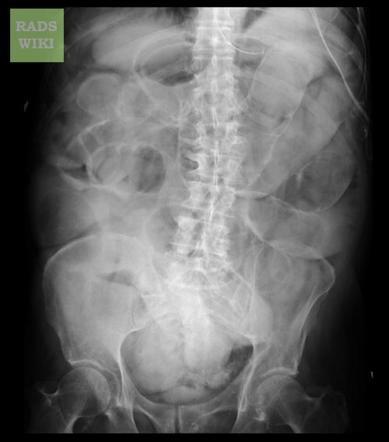

How to approach a AXR?

Image quality

BBC approach:

Bowel + other organs

Bones

Calcification

What is the 3/6/9 rule?

Diameter of intestines should be no greater than:

3cm in small bowel

6cm for colon

9cm for caecum

How does small bowel obstruction appear?

>3cm dilation

Dilated loops = coiled spring look